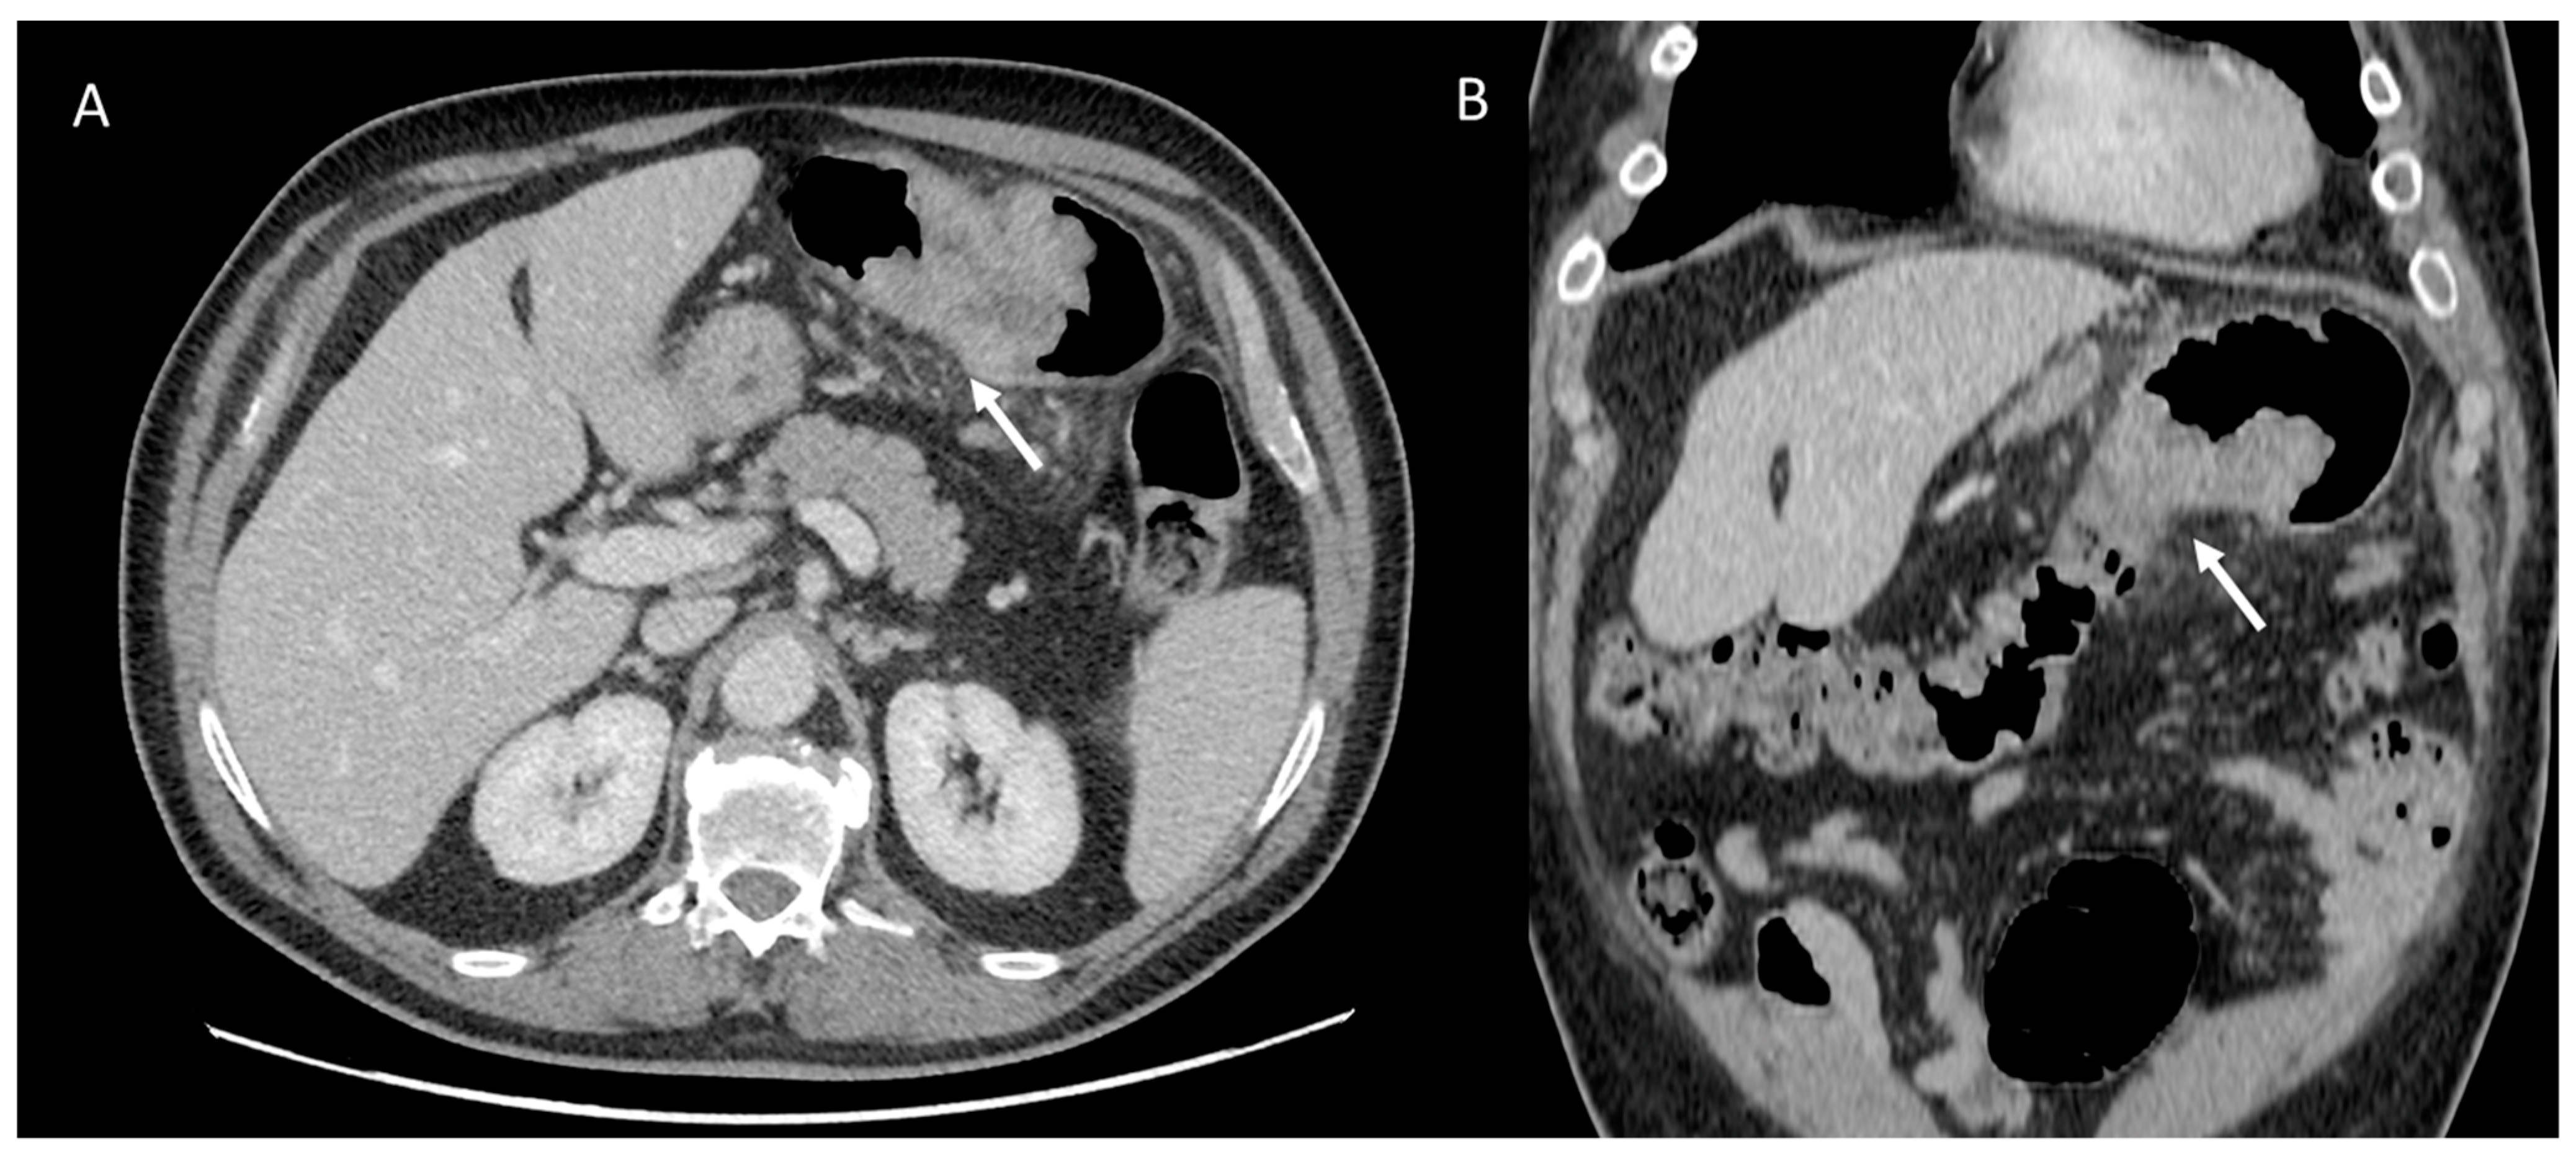

Kim et al. [29] in a study evaluated gender differences regarding the distribution and prevalence of CAC, its relationship to clinical risk factors, and the effect of a high calcium score (≥100) on subsequent initiation of medical therapy by evaluating a court of 542 individuals, of whom 279 were female and 263 were male. The data demonstrated an increasing CAC score with age, regardless of sex. However, women showed significantly lower CAC scores than men in the same age group. The lower CAC scores in women are likely in part indicative of the fact that women have a greater amount of non-calcifying plaque, so-called low-attenuation plaque, than men, indicating that lower CAC scores may actually be related to higher-risk plaque. However, there are also cases, although less frequent, of men with low-attenuation atheromasic plaque (Figure 1). Another interesting finding emerged from the correlation between CAC and clinical risk factors: for both sexes, age had a similar effect on CAC score (OR 1.11 and 1.12, respectively); however, in men, obesity showed a significant effect on CAC score (OR 2.16), while in women, smoking showed a significant effect on CAC score (OR 4.27). This result clearly demonstrated that the traditional clinical risk factors and which women, therefore, share with men actually have different clinical impact in the two genders. Finally, it was investigated how the CAC score result affected the further management of men vs. women with a CAC score ≥100 when adjusted for concurrent coronary CTA findings (moderate to severe lesions vs. non-obstructive lesions) in initiating aspirin and statin therapy [29].

Figure 1.

Male, 39-years-old, patients with history of dyslipidemia, type-1 obesity, and higher level of stress at work. The patient reported a non-anginal chest pain for which an ergometric ECG stress test was performed, and the results were negative. According to the Diamond–Forrester score, the patient was first categorized as a low pre-test probability risk of having CAD. To correctly rule-out CAD, the patients underwent CCTA examination, which showed a severe non-calcific plaque in the distal right coronary artery (white arrowhead).